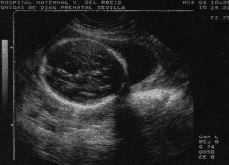

Gestante de 28 años, primigesta, sin antecedentes patológicos de interés, remitida con 27 semanas de amenorrea a nuestra Unidad por sospecha de polihidramnios y quiste cerebral. En la exploración ecográfica se observó un feto único concordante con amenorrea y cantidad de líquido abundante sin llegar a polihidramnios. Intracranealmente se visualizó una imagen quística ventral al cerebelo sin deformarlo y una cisterna magna normal (Fig. 1). Se informó a la gestante de la utilidad de una amniocentesis para descartar anomalías cromosómicas, que la mujer no aceptó. En la revisión practicada a las 32 semanas se observó retraso del crecimiento intrauterino (RCIU), microcefalia relativa, comunicación interventricular y genitales ambiguos, hallazgos compatibles con malformación sindrómica. A las 36 semanas de gestación, la biometría ecográfica demostró un RCIU más marcado junto a los signos ecográficos ya descritos. Tras una inducción a las 41 semanas por prueba de oxitocina patológica, la gestante dio a luz a un recién nacido mujer viva de 2.400 gramos mediante parto fórceps por bradicardia en expulsivo. La niña fue ingresada en pediatría por bajo peso y cuadro malformativo. El estudio de la paciente confirmó las malformaciones sospechadas ecográficamente (Fig. 2). El resultado del estudio citogenético realizado por el cuadro malformativo fue de síndrome de Edwards (47, XX, + 18).

Figura 1. Corte axial de la cabeza fetal a nivel de la fosa posterior donde se observa el quiste aracnoideo.